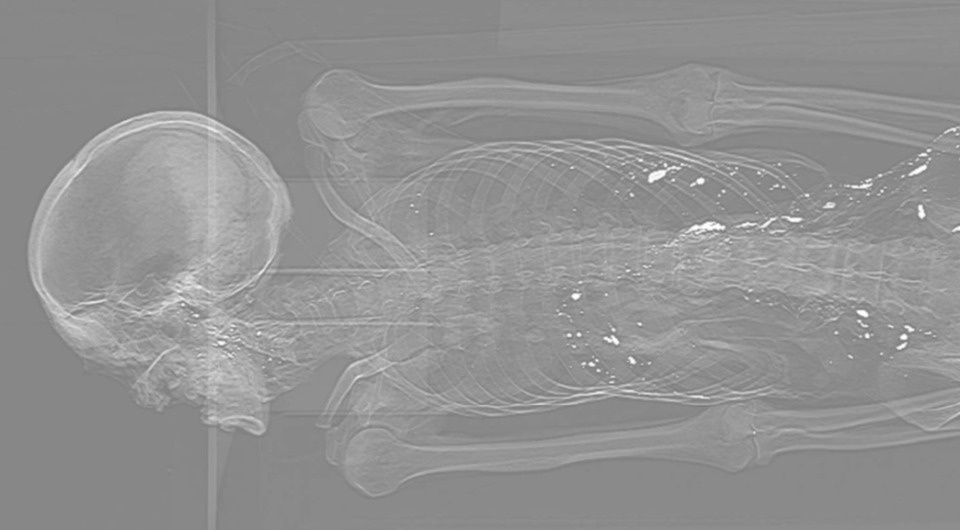

Антропологи и генетики провели комплексный анализ средневековых мумифицированных останков из элитарного захоронения, относящегося к XIII веку нашей эры, которое археологи раскопали в китайском городе Чанчжоу. Исследователи определили, что останки принадлежали пострадавшему от атеросклероза мужчине, тело которого забальзамировали после смерти, для чего в его кишечник ввели раствор, содержащий киноварь. Об этом они пишут в статье, опубликованной в Journal of Genetics and Genomics.